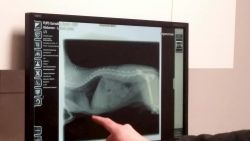

Zunächst zeigte uns Herr Gorzolka die Behandlungsräume und erklärte uns das Röntgengerät. Man muss eine Platte auf den Röntgentisch legen und ein „Foto“ auslösen. Dann kann man auf dem Computer das Röntgenbild sehen. Er hat uns ein Röntgenbild von seiner Katze gezeigt. Man konnte das Skelett sehen. Außerdem hat man einen Chip gesehen. Damit kann ein Arzt, die Feuerwehr oder ein Tierheim ablesen, wem das Tier gehört und dann den Besitzer oder die Besitzerin anrufen.